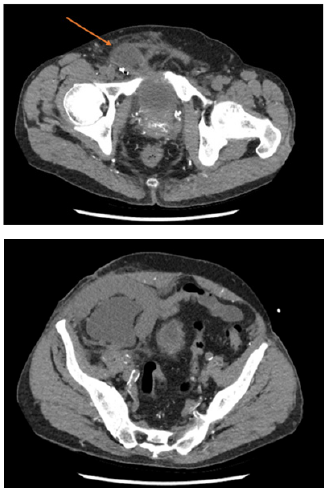

CT one week later demonstrated significant improvement in the hydroureteronephrosis of the transplanted kidney (Figure 3). He was continued on antibiotic therapy and scheduled for follow up for the repair of his inguinal hernia upon resolution of his urosepsis. His PCNU catheter was to remain in place until surgical repair of the hernia.